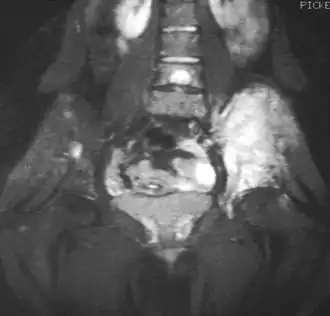

La resonancia magnética (IRM) podría ser usada rutinariamente en la investigación de los tumores malignos. La IRM mostrará la extensión total del tejido óseo y los tejidos blandos y establece la relación del tumor a las estructuras anatómicas cercanas (e.j. vasos sanguíneos).[14][15] Algunos investigadores sostienen que la IRM mejorada con contraste puede ayudar a determinar la cantidad de necrosis dentro del tumor, esto ayuda a determinar la respuesta al tratamiento antes de la cirugía.[15]